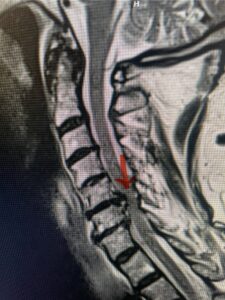

The case illustrates a more subtle finding of cervical myelopathy in a young 52 year-old male who presents with 5 months of left upper extremity weakness and burning. He also had developed over the last two months pain in his right upper extremity. He also had difficulty with fine motor skills. He had a positive Hoffman reflex and mild 4-4+ long tract weakness of his left arm and leg. Cervical MRI revealed an explanation for the patient’s symptoms (Fig. 7) as it revealed a disc osteophyte complex causing some cord flattening, slightly more to the left. We performed a C5-6 anterior cervical discectomy and interbody fusion with cage and plate (Fig. 8) He had a significant improvement in his weakness, numbness, and pain. What is interesting is that this was a relatively young patient without severe cord compression but was significantly affected by a mild amount of cord compression. This may speak to how a younger spinal cord may react much more adversely perhaps secondary to a less compliant spinal cord.

Fig. 7a Sagittal and axial T2-weighted cervical MRI’s demonstrating spinal cord compression slightly to the left secondary to disc/osteophyte complex (red arrow)